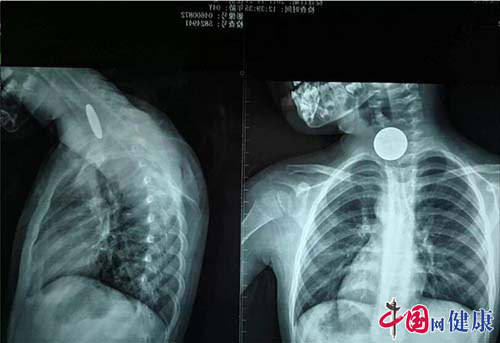

中国网健康讯 “医生,快看看我的孩子!”这么焦急的声音,到底发生了什么事?原来,11月27日上午11点,一个4岁的女孩独自玩耍时不小心吞下了一枚1元硬币,家长发现后立即将小孩送到柳州市人民医院急诊科就诊。在为女孩做了颈部和胸部的X光片检查后,医生发现硬币卡在女孩的食道中间的狭窄段(注:非进食状态下食道呈闭合状)。

术前,女孩看到很多的医生围着自己,心里很害怕,不敢接受手术,医生就和她的父母一起安慰她,慢慢的,女孩的情绪平稳了。为提高手术的成功率,也避免伤害到孩子的食道,田医生决定从女孩的鼻腔插入气囊导尿管。女孩在医生的安抚下,非常配合。田医生根据X光片和经验判断,将气囊导尿管伸到合适的深度,然后开始向导管的气囊里充气,之后利用气囊将硬币推出,不久后女孩成功吐出硬币,手术顺利的结束了,整个过程仅持续了几分钟。